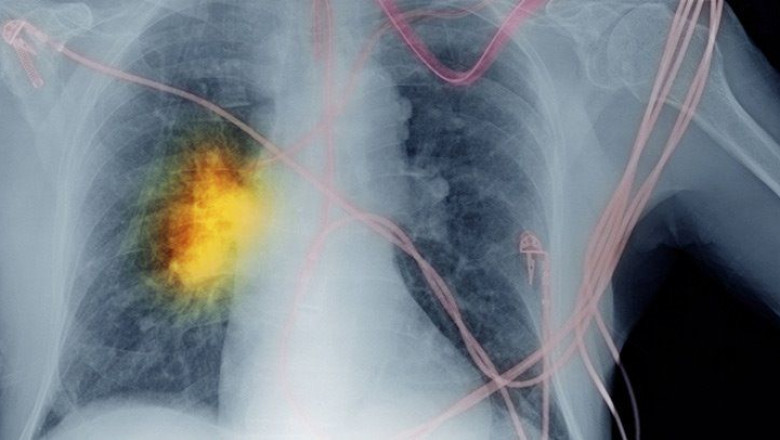

Europe non-small cell lung cancer diagnostics market is expected to reach USD 846.60 million by 2028 from USD 331.31 million in 2020, growing at a steady CAGR of 12.5% in the forecast period of 2021 to 2028.

Some of the major players operating in the non-small cell lung cancer diagnostics market are Abbott Laboratories, F. Hoffmann-La Roche Ltd, Agilent Technologies, Inc., QIAGEN, Quest Diagnostics Incorporated, NeoGenomics Laboratories, Inc., NanoString, Janssen Pharmaceutical NV, Inivata Ltd, bioMérieux SA, OncoCyte Corporation Inc., GENERAL ELECTRIC COMPANY, Eckert & Ziegler, Dr. Lal PathLabs, RIVERAIN TECHNOLOGIES